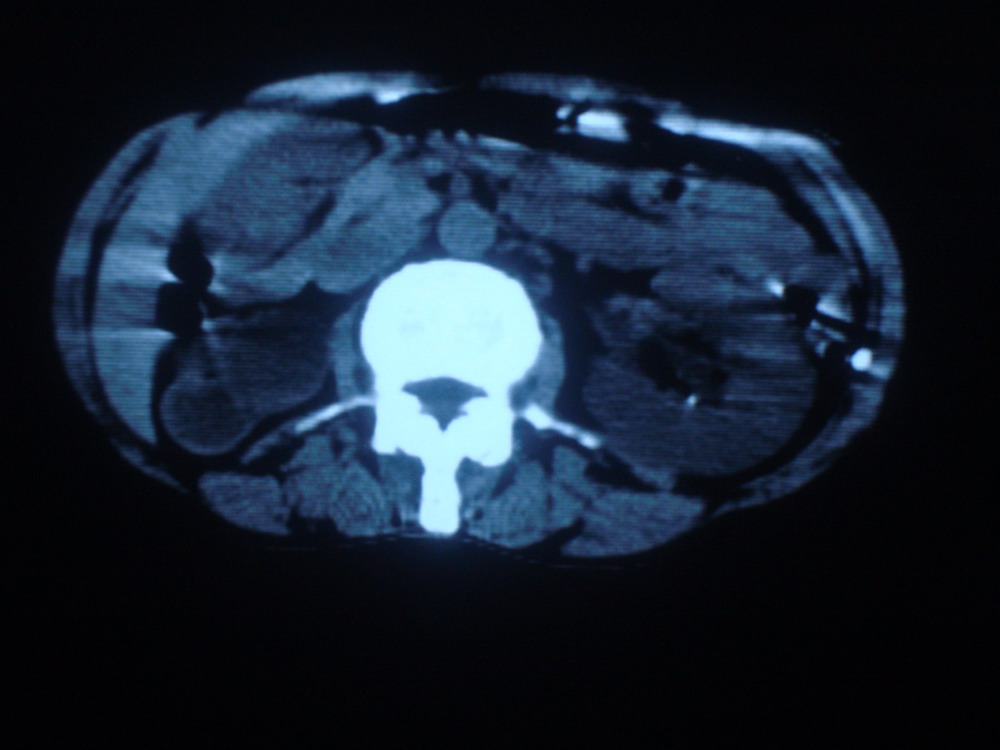

以下是引用卜一在2009-4-1 19:39:00的发言:[br]右肾发育不全、结石、积水并感染可能;左肾结石,代偿性增大。支持!

以下是引用随缘的人在2009-4-1 20:42:00的发言:[br]右肾发育不全、结石、积水并感染可能;左肾结石,代偿性增大。支持!